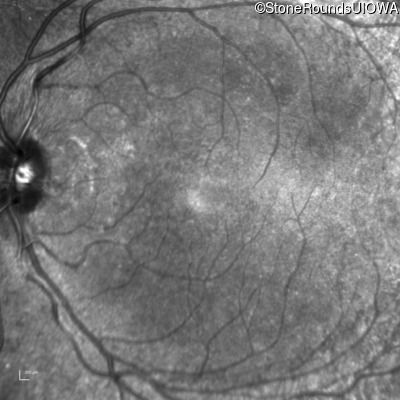

Infrared Fundus Photograph - Left - 20/20 -1

Exemplar